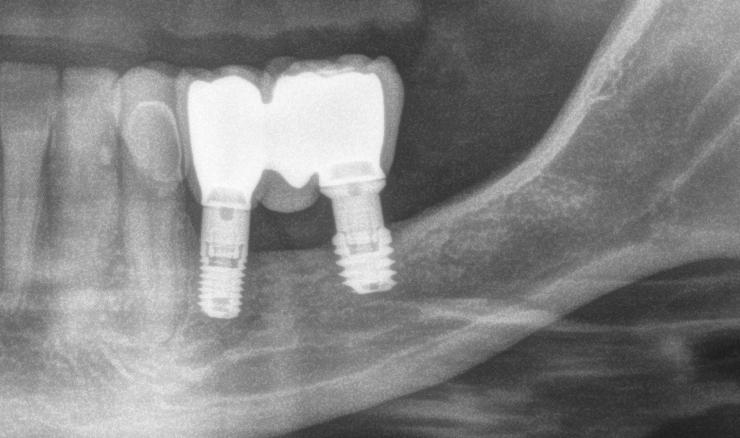

3. Análisis radiográfico y tomográfico (Ilustración 4):

 Constricción maxilar con deficiencia transversal

> 5 mm.

 Clase III esquelética.

 Patrón esquelético hiperdivergente con el plano oclusal mandibular compensado con rotación anti-horaria.

 Sutura palatina media parcialmente osificada (8) (9).

 Posición de terceros molares no favorable, por lo que se recomendó extracción.

Ilustración 4. Registros radiográficos iniciales de estudio.

 La expansión obtenida fue > 5 mm, evidenciada en la tomografía post-tratamiento.

Ilustración 11. Izquierda: CBCT y radiografía panorámica post-tratamiento. Derecha: superposición del CBCT inicial y final.